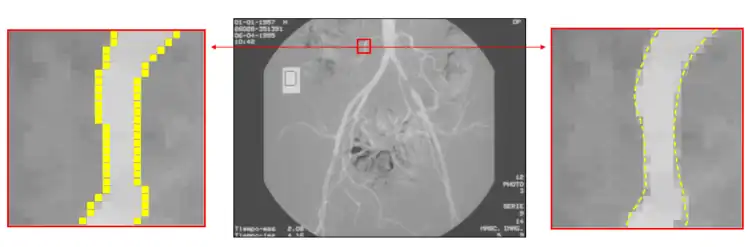

Subpixel

To increase the precision of edge detection, several subpixel techniques had been proposed, including curve-fitting, moment-based,[23][24] reconstructive, and partial area effect methods.[25] These methods have different characteristics. Curve fitting methods are computationally simple but are easily affected by noise. Moment-based methods use an integral-based approach to reduce the effect of noise, but may require more computations in some cases. Reconstructive methods use horizontal gradients or vertical gradients to build a curve and find the peak of the curve as the sub-pixel edge. Partial area effect methods are based on the hypothesis that each pixel value depends on the area at both sides of the edge inside that pixel, producing accurate individual estimation for every edge pixel. Certain variants of the moment-based technique have been shown to be the most accurate for isolated edges.[24]